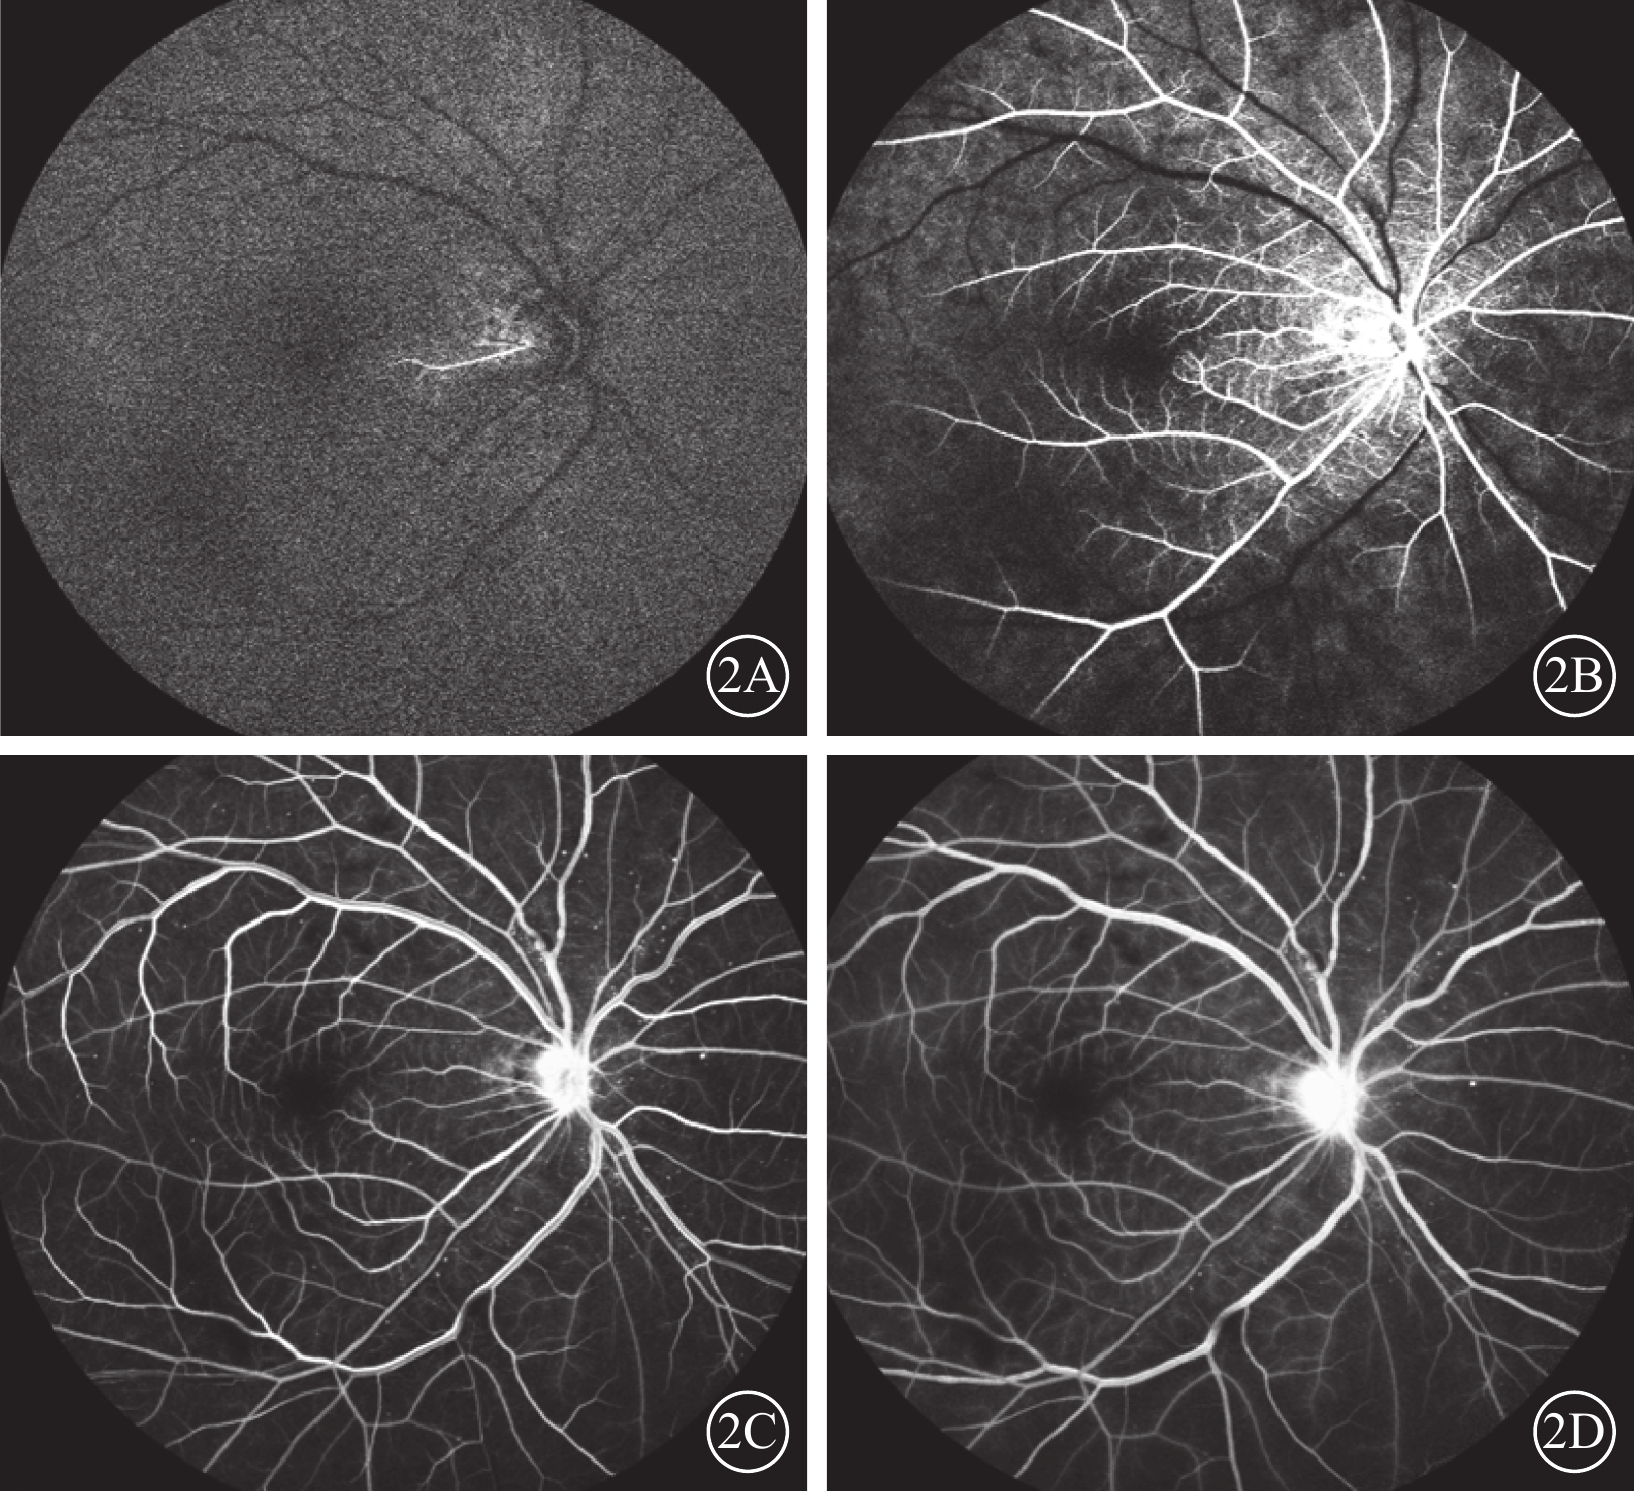

患者男,65歲。因右眼視物不見1周于2016年10月20日來我院就診。1周前無意中發現右眼視物不見,無眼紅、痛、畏光、流淚;自行使用芐達賴氨酸(商品名:莎普愛思)滴眼液滴眼無效而就診于外院。診斷為右眼新生血管性青光眼(NVG)?右眼視網膜病變(性質?);雙眼老年性白內障。既往高血壓病史8年,口服藥物治療。否認糖尿病、冠心病等其他全身病史。眼科檢查:右眼視力光感/眼前;左眼視力0.6,不能矯正。右眼眼壓17.3 mmHg(1 mmHg= 0.133 kPa),左眼眼壓12.7 mmHg。右眼前房深淺正常,周邊前房1 角膜厚度;瞳孔藥物性散大,邊緣全周可見虹膜新生血管(NVI),無后粘連;晶狀體混濁;玻璃體輕度混濁。眼底視盤邊界清楚,顏色橘紅,血管走形及比例基本正常;視網膜可見散在點片狀出血及片狀棉絨斑,黃斑中心凹反光不清(圖1)。左眼除晶狀體混濁、玻璃體輕度混濁,黃斑中心凹反光不清外,其余眼前節及眼底檢查未見明顯異常。熒光素眼底血管造影(FFA)檢查,右眼脈絡膜背景熒光充盈遲緩,視網膜動靜脈循環時間明顯延長(圖2)。光相干斷層掃描檢查,右眼后極部視網膜增厚,視網膜內層間反射信號大部分增強;左眼黃斑中心凹形態不規則。彩色超聲多普勒血流成像(CDFI)檢查,雙側頸總動脈、頸內動脈多發斑塊;右側頸內動脈管腔狹窄,約70%~99%(圖3)。頸動脈CT血管造影(CTA)檢查,顱內動脈硬化,可疑右側頸內動脈C1段重度狹窄;可疑兩側基底節區、右側丘腦腔隙性缺血灶。診斷:右眼眼缺血綜合征(OIS);雙眼老年性白內障;高血壓病。給予右眼玻璃體腔注射雷珠單抗0.05 ml治療。治療后3 d,視力數指/66 cm,眼壓15.0 mmHg;NVI完全消退。行右眼全視網膜激光光凝(PRP)治療。PRP治療后14 d檢查,右眼視力0.1;眼壓13.0 mmHg。轉血管外科行右側頸動脈內膜剝脫手術。手術后1個月復查,右眼視力0.4。FFA檢查,視網膜循環時間明顯改善(圖4)。

右眼FFA像。2A. 15.28 s,可見視網膜中央動脈充盈前峰;2B. 23.85 s,視網膜中央動脈完全充盈;2C. 44.59 s,視網膜靜脈層流;2D. 1 min 54.09 s,視網膜靜脈完全充盈

右眼FFA像。2A. 15.28 s,可見視網膜中央動脈充盈前峰;2B. 23.85 s,視網膜中央動脈完全充盈;2C. 44.59 s,視網膜靜脈層流;2D. 1 min 54.09 s,視網膜靜脈完全充盈

患者男,65歲。因右眼視物不見1周于2016年10月20日來我院就診。1周前無意中發現右眼視物不見,無眼紅、痛、畏光、流淚;自行使用芐達賴氨酸(商品名:莎普愛思)滴眼液滴眼無效而就診于外院。診斷為右眼新生血管性青光眼(NVG)?右眼視網膜病變(性質?);雙眼老年性白內障。既往高血壓病史8年,口服藥物治療。否認糖尿病、冠心病等其他全身病史。眼科檢查:右眼視力光感/眼前;左眼視力0.6,不能矯正。右眼眼壓17.3 mmHg(1 mmHg= 0.133 kPa),左眼眼壓12.7 mmHg。右眼前房深淺正常,周邊前房1 角膜厚度;瞳孔藥物性散大,邊緣全周可見虹膜新生血管(NVI),無后粘連;晶狀體混濁;玻璃體輕度混濁。眼底視盤邊界清楚,顏色橘紅,血管走形及比例基本正常;視網膜可見散在點片狀出血及片狀棉絨斑,黃斑中心凹反光不清(圖1)。左眼除晶狀體混濁、玻璃體輕度混濁,黃斑中心凹反光不清外,其余眼前節及眼底檢查未見明顯異常。熒光素眼底血管造影(FFA)檢查,右眼脈絡膜背景熒光充盈遲緩,視網膜動靜脈循環時間明顯延長(圖2)。光相干斷層掃描檢查,右眼后極部視網膜增厚,視網膜內層間反射信號大部分增強;左眼黃斑中心凹形態不規則。彩色超聲多普勒血流成像(CDFI)檢查,雙側頸總動脈、頸內動脈多發斑塊;右側頸內動脈管腔狹窄,約70%~99%(圖3)。頸動脈CT血管造影(CTA)檢查,顱內動脈硬化,可疑右側頸內動脈C1段重度狹窄;可疑兩側基底節區、右側丘腦腔隙性缺血灶。診斷:右眼眼缺血綜合征(OIS);雙眼老年性白內障;高血壓病。給予右眼玻璃體腔注射雷珠單抗0.05 ml治療。治療后3 d,視力數指/66 cm,眼壓15.0 mmHg;NVI完全消退。行右眼全視網膜激光光凝(PRP)治療。PRP治療后14 d檢查,右眼視力0.1;眼壓13.0 mmHg。轉血管外科行右側頸動脈內膜剝脫手術。手術后1個月復查,右眼視力0.4。FFA檢查,視網膜循環時間明顯改善(圖4)。

右眼FFA像。2A. 15.28 s,可見視網膜中央動脈充盈前峰;2B. 23.85 s,視網膜中央動脈完全充盈;2C. 44.59 s,視網膜靜脈層流;2D. 1 min 54.09 s,視網膜靜脈完全充盈

右眼FFA像。2A. 15.28 s,可見視網膜中央動脈充盈前峰;2B. 23.85 s,視網膜中央動脈完全充盈;2C. 44.59 s,視網膜靜脈層流;2D. 1 min 54.09 s,視網膜靜脈完全充盈